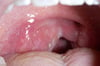

咽頭の直接的な診察では,扁桃周囲または咽後領域の発赤,滲出液,および腫脹の徴候に注意すべきである。口蓋垂が正中線上にあるか,または片側に押されているように見えるかにも注意すべきである。

咽頭膿瘍および扁桃咽頭炎は,咽頭の発赤,滲出液,またはその両方を引き起こす場合がある。しかし,一部の所見はいずれか一方の疾患で生じる可能性がより高い:

• 咽頭膿瘍:くぐもった,「熱いジャガイモが口に入っているような」声(あたかも熱い物が口の中に入っているように話す)および咽頭後壁の明らかな局所腫脹(しばしば口蓋垂の偏位を伴う)

• 扁桃咽頭炎:しばしばURIの症状(例,鼻汁,咳嗽)

扁桃咽頭炎は臨床的に容易に認識されるが,原因の同定は容易ではない。ウイルス感染症とGABHS感染症の症状は著しく重複しているが,ウイルス性の原因ではURIの症状がより一般的である。成人では,原因としてGABHSの疑いが強まる臨床基準には以下のものがある:

• 扁桃滲出物